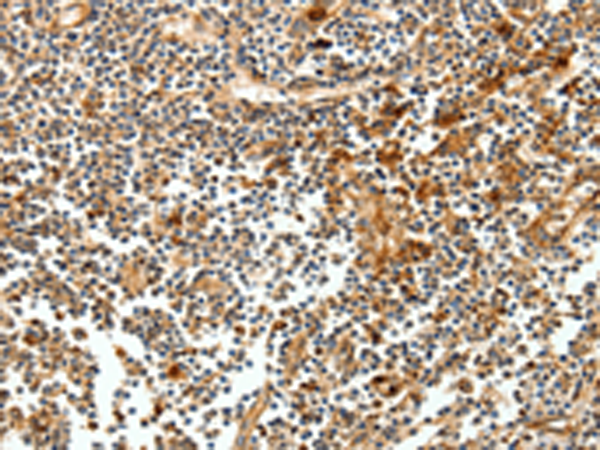

分类: 科研抗体货号: P07204别名: CLAX; LLT1; OCIL应用: IHC反应种属: Human